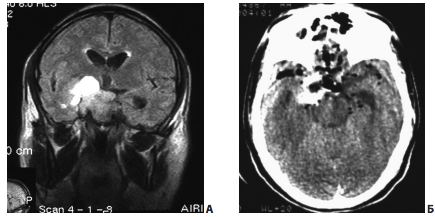

Рис. 8. Пример удаления эндо-супра-латероселлярной аденомы (от кавернозного синуса отходит вторичный узел опухоли): А, Б — МРТ до операции; В — интраоперационное фото; стрелкой указано переднее колено левой сонной артерии; Г — интраоперационное фото; стрелкой указана полость вторичного узла; Д, Е — интраоперационное фото; этапы удаления опухоли из полости вторичного узла

Нередко вторичные узлы опухоли отходят не от супраселлярной части, а от раздутого аденомой кавернозного синуса. В этих случаях удаление вторичных узлов становится возможным лишь после более или менее радикального удаления аденомы из полости кавернозного синуса (рис. 10).

Рис. 10. Пример удаления эндо-супра-латероселлярной аденомы: А — МРТ до операции; от верхней стенки синуса отходит вторичный узел опухоли; Б — МРТ после операции; явных остатков опухоли не определяется

На рис. 11 представлен пример удаления гигантской эндо-супра-латероселлярной аденомы гипофиза — от задне-верхних отделов левого кавернозного синуса формировался крупный вырост опухоли с признаками старого кровоизлияния в него

Рис. 11. Пример удаления гигантской эндо-супра-латероселлярной аденомы: А, Б — КТ до операции; В, Г — МРТ до операции, Д, Е — МРТ через несколько месяцев после операции

Первым этапом была удалена эндо-супраселлярная часть опухоли под контролем 0 и 30-градусных эндоскопов. Затем под контролем 45º и 70º эндоскопов опухоль удалена из полости левого кавернозного синуса, в задних отделах синуса обнаружен вторичный узел опухоли, из его полости выделилось некоторое количество темно-бурой жидкости, после чего со стенок вторичного узла удалено небольшое количество опухоли (рис. 11, 12). При контрольной МРТ через несколько месяцев после операции явные остатки опухоли, в том числе и в полости кавернозного синуса, не определяются. Стрелкой указана складка капсулы удаленного вторичного узла.На рис. 13 представлен пример удаления большой эндо-супра-латероселлярной аденомы гипофиза. Однако, по данным контрольной КТ в первые сутки после операции, можно лишь сказать, что нами была удалена большая часть опухоли, но судить о том, есть ли остатки аденомы и какого они размера, достаточно сложно.

Рис. 12. Интраоперационный снимок этапа удаления гигантской эндо-супра-латероселлярной аденомы (45º эндоскоп): 1 — проекция левого зрительного нерва; 2 — капсула супраселлярного отдела опухоли; 3 — задне-верхние отделы левого кавернозного синуса